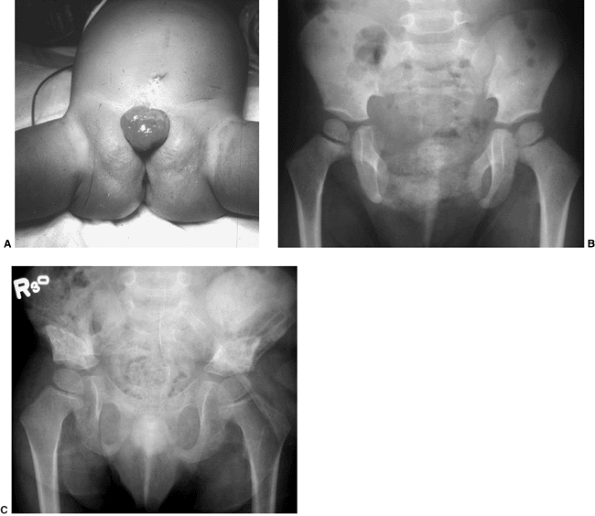

![]() |

Figure 27.18 Patient with severe multiple neurologic and pelvic anomalies associated with cloacal exstrophy. (Courtesy of Paul Sponseller.)